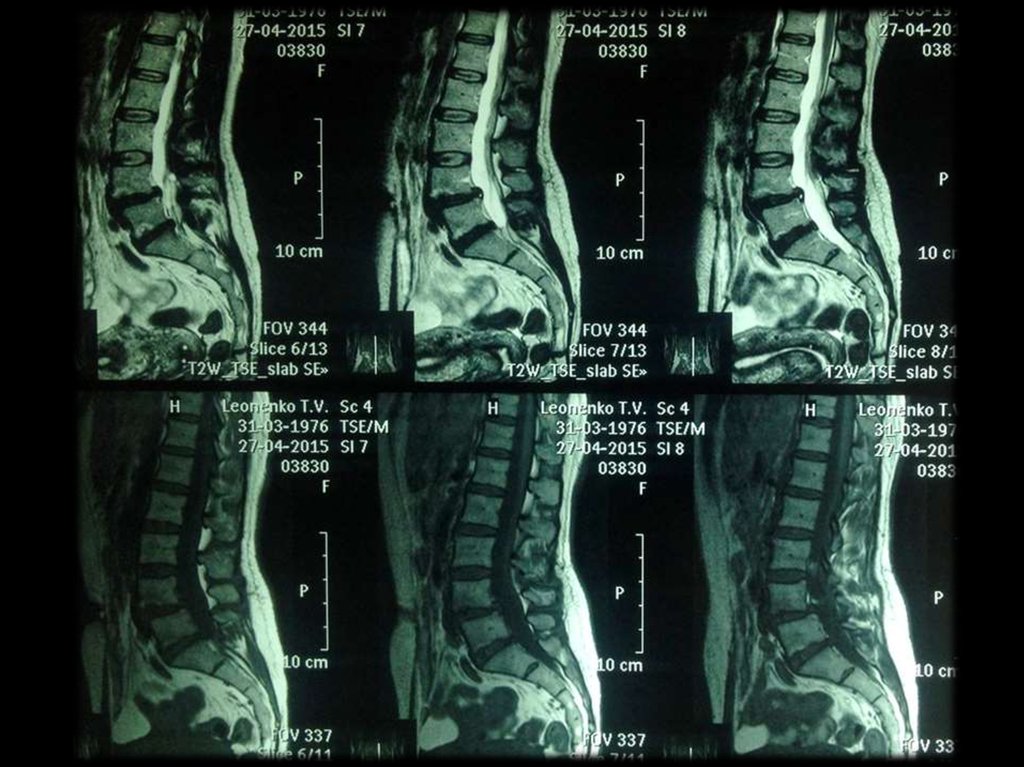

СТЕПЕНИ ДЕГЕНЕРАЦИИ МПД В СРАВНЕНИИ ПРИ

МАКРОСКОПИЧЕСКОМ И РЕНТГЕНОЛОГИЧЕСКОМ

ОБСЛЕДОВАНИЯХ

ДЕГЕНЕРАТИВНО-ДИСТРОФИЧЕЕСКИЕ ИЗМЕНЕНИЯ

ПОЗВОНОЧНИКА (СХЕМА)

1 – Остеофиты

2 – Грыжи Шморля

3 – Обызвествление диска

4 – Передние остеофиты

5 – Субхондральный склероз

6 – Сужение межпозвонковой щели

7 – Задний остеофит

8 – Клиновидная деформация

позвонка

9 – Сужение межпозвонкового

отверстия